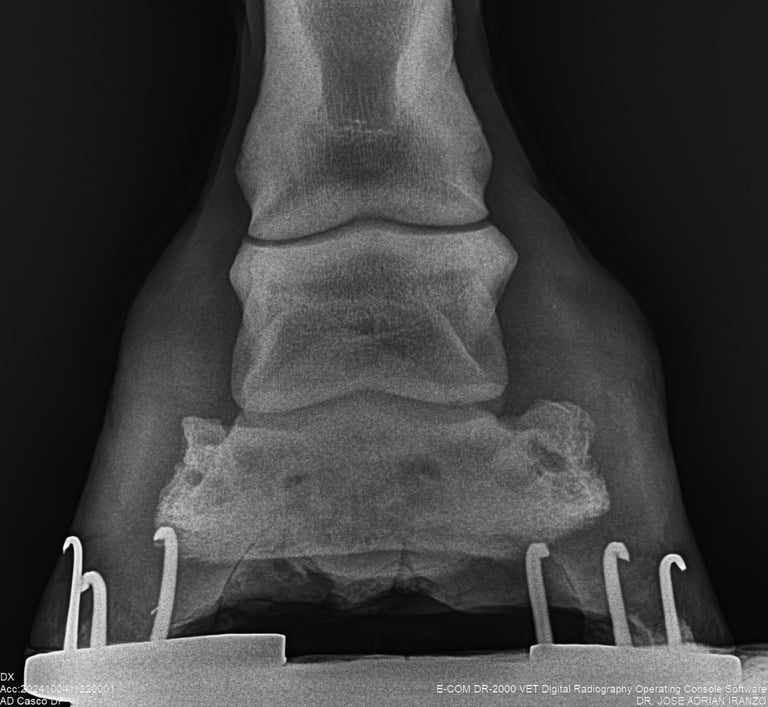

DIAGNOSTICO POR IMAGENES: ECOGRAFIA Y RADIOGRAFIA